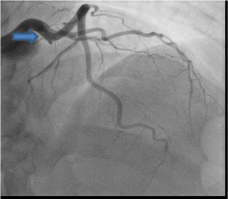

Patient was taken for emergent cardiac catheterization that showed 100% stenosis in proximal left anterior descending artery with TIMI 0 flow (Figure 2 and 3). There were abundant collaterals from RCA to septum (Figure 4). Due to late presentation MI with Q waves on EKG, PCI was deferred. Patient was started on aspirin, clopidogrel, carvedilol, high-intensity statin and unfractionated heparin and was admitted to coronary care unit for further management and observation.

Figure 4. Coronary Angiogram in Right Anterior Oblique (RAO) Cranial view with collateral blood vessels from RCA to LAD as indicated by arrow